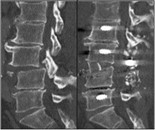

Abbildung 1: Das Bild zeigt eine Luxationsfraktur L3/4 vor und nach operativer Versorgung.

Individuell legen wir fest, ob bei Ihnen ein Operationsverfahren von hinten/ von dorsal, von der Seite/ lateral oder von vorne/ ventral angewendet werden sollte. Manchmal setzen wir auch kombinierte Verfahren ein. Unser Ziel ist dabei immer, die verletzten Wirbelsäulenabschnitte optimal zu rekonstruieren und die neurologischen Funktionen zu erhalten.